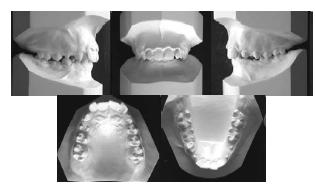

enunciado 287435-1

As figuras apresentadas acima apresentam os moldes das arcadas dentárias de um paciente. Assinale a opção correta quanto à fase da dentição em que o paciente se encontra e o tipo de má oclusão apresentado, de acordo com a classificação proposta por Angle.